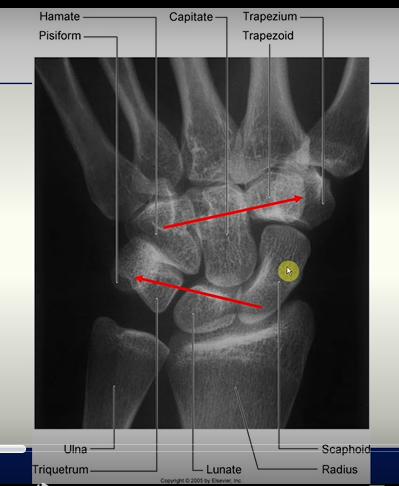

X - RAY

Wrist Joint

Articulation between;

the distal end of the radius and the articular disc overlying the distal end of the ulna

ellipsoid concave

scaphoid and lunate

ellipsoid convex

Radius

the scaphoid and the lunate articulate with the radius

sometimes a small part of the triquetrum may articulate with the articular disc of the distal radio-ulnar joint, but not directly with the radius itself

Ulna

the ulna does not directly articulate with any carpal bone.

instead, the triangular fibrocartilage complex (TFCC) sits between the ulna and the proximal carpal row (mainly the triquetrum and lunate)